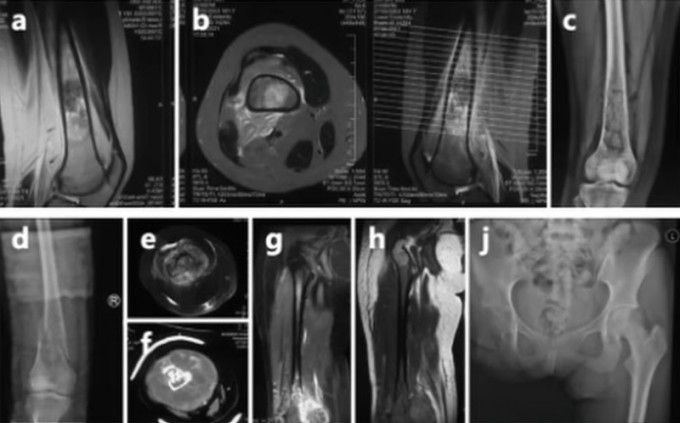

Phim chụp ung thư xương của Thế Vĩ. Ảnh: The Paper